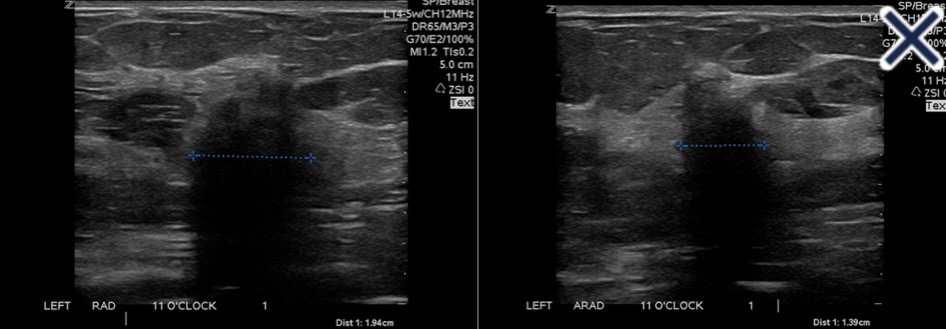

• The suppression of speckle artifact by coded harmonics makes solid nodules more hypoechoic and conspicuous than they are with fundamental imaging (Images)

Infiltrating ductal carcinoma with fundamental imaging.

The same infiltrating ductal carcinoma as above with coded harmonic imaging